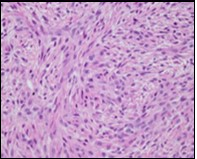

The neoplasm frequently infiltrates abutting skeletal muscle. Occasionally, tumefaction denominates hyper-cellular foci, tumour necrosis, cellular or nuclear atypia and mitotic figures, features which are characteristic of intermediate to high grade sarcoma. Localized tumour reoccurrence may be hyper-cellular with enhanced mitotic activity 4, 5. On ultrastructural examination, fibroblastic differentiation is exemplified 5. Figure 1, Figure 2, Figure 3, Figure 4, Figure 5, Figure 6, Figure 7, Figure 8.

Figure 1.Low grade fibromyxoid sarcoma enunciating fibrous and myxoid zones of uniform spindle-shaped tumour cells with absence of atypia 9.